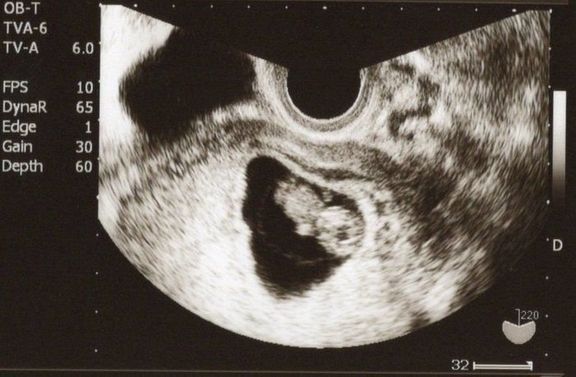

"おなかの中はどうなっていくの? エコー写真で振り返る、高齢ママのはじめての妊娠生活" -

妊娠後期、赤ちゃんが育っていない? エコー写真で振り返る3人目の出産体験 -

おなかの中にいる時からそっくり! 今見ても笑っちゃう【第1子エコー写真】 -

思いがけず授かった2人目は43歳の高齢出産!健診は不安と期待との板挟み! -

推定体重は3773g!骨盤に入らず緊急帝王切開になった長女の成長をエコー写真で振り返る